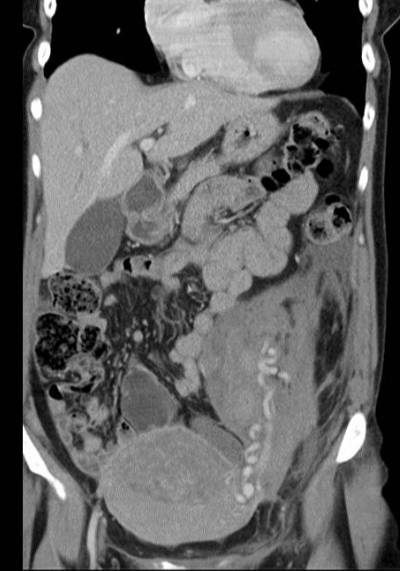

所有年龄超过 40 岁的患者, 卵巢受损 14%-43% 研究中闭经发生率(15%)与单纯UAE报告相似,可能与患者年龄(≥45岁)及卵巢储备自然下降有关。 ![]() 50岁,长期因子宫肌瘤导致月经出血过多,痛经和贫血。 子宫肌瘤栓塞术前,显示双侧子宫动脉发育不全,子宫肌瘤双侧卵巢动脉。 经皮股动脉穿刺双侧卵巢动脉栓塞,先500μm-700μm emboSphere 微球 术后4周,和6月的中短期随访,月经正常,子宫容积减少,贫血纠正,无卵巢功能衰竭。但看起来非灌注容积较少。 术后9月,由于子宫肌瘤持续存在,患者自己希望绝经,行全子宫和双侧卵巢切除术 术后病理,子宫内可见栓塞微粒伴有坏死,卵巢内也见栓塞微粒,但卵巢功能未受损。